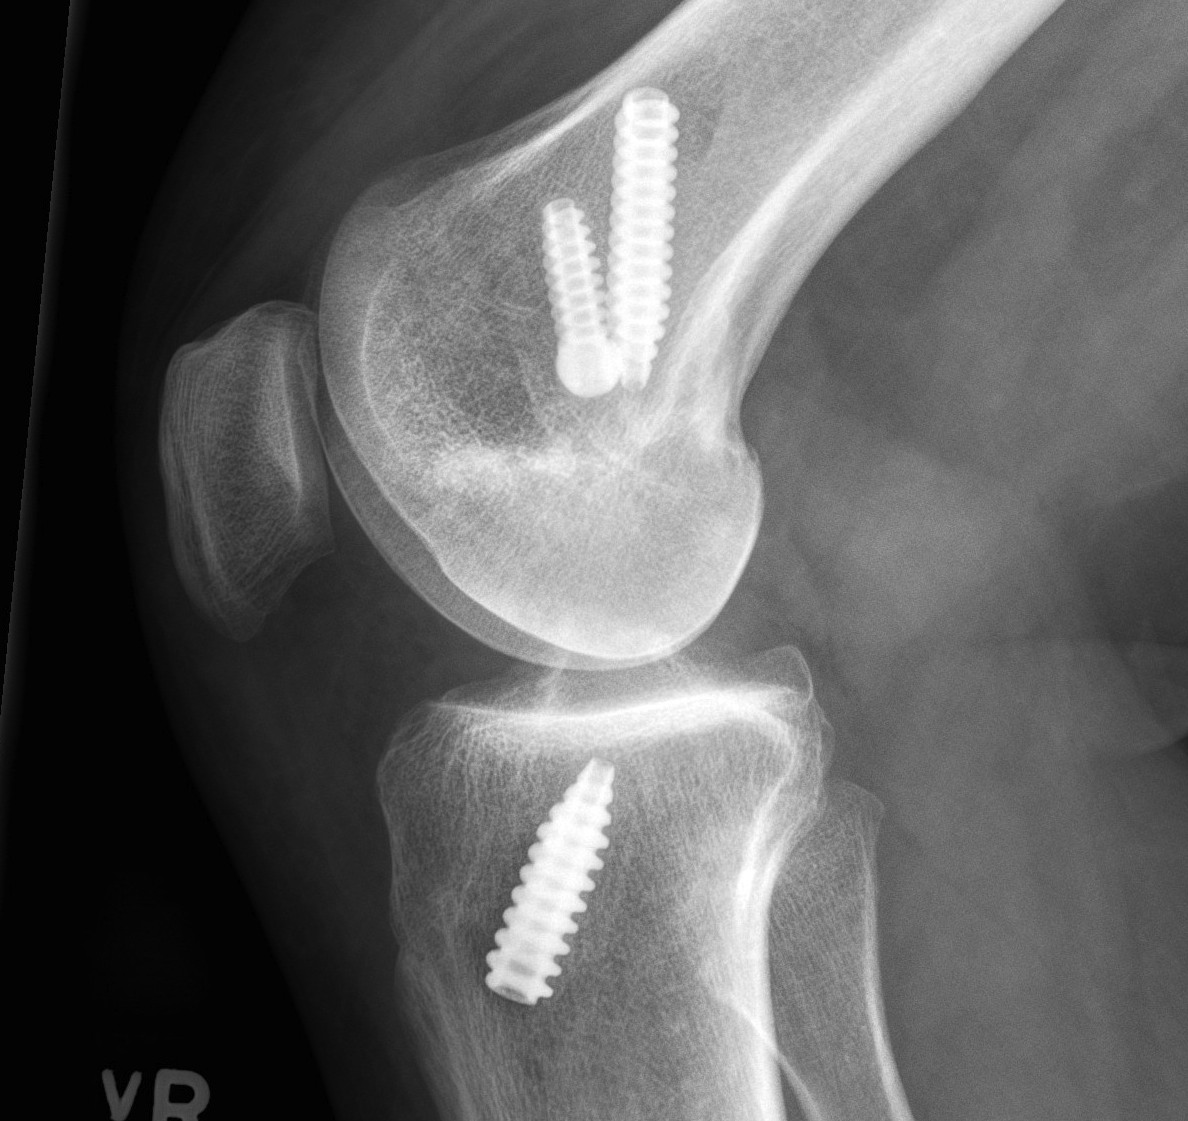

Xray

AP and Lateral

- assess tunnel placement

- Assess metal work

- types of fixation

- metal v plastic